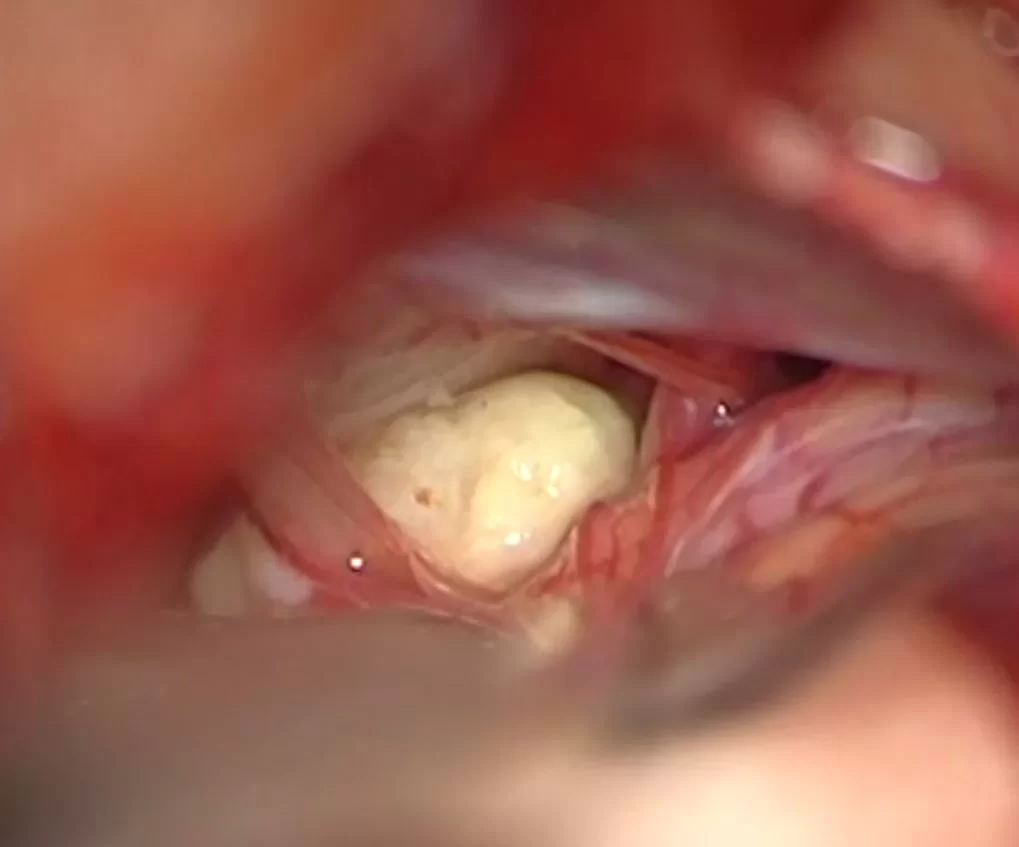

Οι επιδερμοειδείς κύστεις αντιμετωπίζονται με χειρουργική επέμβαση. Οι κύστεις τείνουν να αναπτύσσονται κατά μήκος των κρανιακών νεύρων, πράγμα που μπορεί να καταστήσει την ολική αφαίρεσή τους δύσκολη. Διεγχειρητικά, έχουν χαρακτηριστική εμφάνιση, σαν “πέρλα” (Εικόνα 1). Για πολλαπλές ή ταχέως επαναλαμβανόμενες επιδερμοειδείς κύστεις έχει περιγραφεί η θεραπεία με ακτινοβολία.